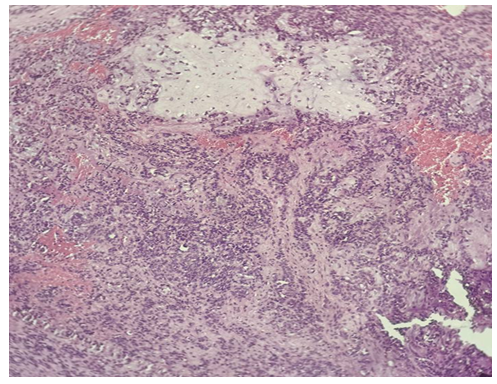

| Picture 4. Surgically resected specimens of salivary gland tumors. Histological appearance of undifferentiated carcinoma (4 cases), localized in the right palatal mucosa (Nos. 1297, 1298) and mandible (Nos. 1383, 1384). The tumor is composed of solid sheets and nests of atypical epithelial cells with a high nuclear–cytoplasmic ratio, marked nuclear pleomorphism, hyperchromasia, and absence of glandular differentiation (H&E stain) |

A total of 48 patients with salivary gland tumors were examined between 2023 and 2025. The cohort included 45 males and 3 females. The most frequent malignant neoplasms were undifferentiated carcinoma (4 cases) and adenocarcinoma, stage I (3 cases). Benign tumors included pleomorphic adenoma (1 case) and monomorphic adenoma (1 case).Histopathological examination revealed distinct morphological patterns characteristic of each tumor type. Representative photomicrographs are presented below. | Figure 1. Undifferentiated carcinoma (H&E stain, ×10) |

Morphological description: Tumor tissue demonstrates a solid growth pattern with sheets of atypical epithelial cells. The cells show high nuclear-cytoplasmic ratio, hyperchromatic nuclei, and loss of normal glandular architecture. Areas of necrosis and irregular stromal infiltration are evident. No clear glandular or squamous differentiation is observed, which corresponds to the diagnosis of undifferentiated carcinoma. Figure 1. Histological section of undifferentiated carcinoma of the salivary gland showing solid sheets of atypical cells with hyperchromatic nuclei and absence of glandular differentiation (H&E stain, ×10). | Figure 2. Undifferentiated carcinoma (mandibular localization, H&E stain, ×10) |

Morphological description: The histological section demonstrates infiltrative tumor growth with dense sheets of atypical epithelial cells. Cells display pleomorphism, irregular nuclear contours, hyperchromasia, and scant cytoplasm. The stroma is fibrous, with focal desmoplastic reaction. No signs of glandular or squamous differentiation are present, which is consistent with the diagnosis of undifferentiated carcinoma of the mandible. Figure 2. Undifferentiated carcinoma of the mandible showing sheets of pleomorphic tumor cells with hyperchromatic nuclei and fibrous stromal reaction. No evidence of glandular or squamous differentiation is observed (H&E stain, ×10). | Figure 3. Monomorphic adenoma (left submandibular gland, H&E stain, ×20) |